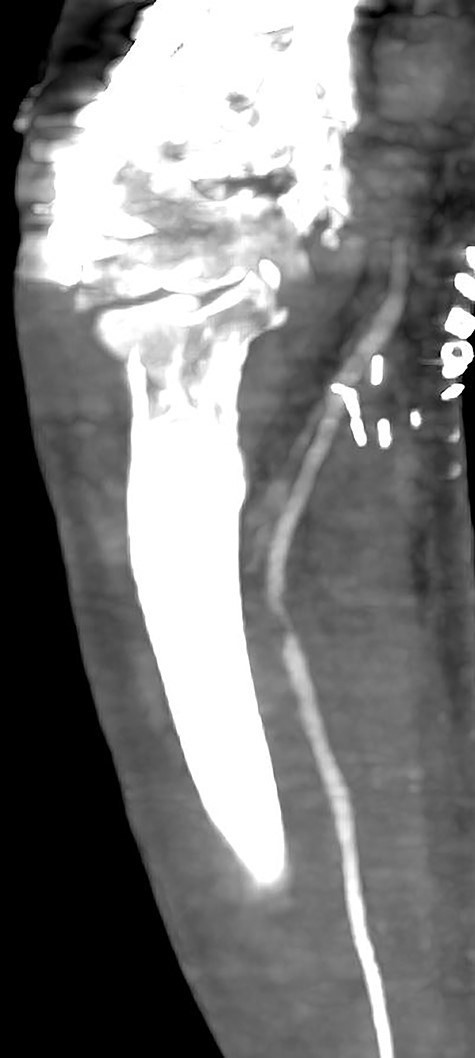

Seven days later, while his general condition was deteriorating, he developed acute ischemia in his right thumb and index finger (Fig. 2). In the ipsilateral forearm, a radial artery catheter had been inserted for monitoring. An urgent radial artery embolectomy was performed and restored the arterial supply to the right hand. The antithrombotic agent was changed to fondaparinux (7.5 mg/once daily). However, within the next few days, it was clinically evident that the revascularization effort was unsuccessful as the thumb and index finger developed dry gangrene. On examination, there was no palpable radial pulse, the ulnar artery pulse was palpable at the level of the wrist and the capillary refill time was normal at the middle, ring and little fingers. A CT angiography (Figs 3 and 4) was performed, demonstrating complete thrombosis of the radial artery beginning at the level of the elbow as well as a 70% occlusion of the ulnar artery ~15 cm proximal to the wrist. Thrombosis of the right axillary vein was also seen (Fig. 5). Orthopedic review was requested for consideration for finger amputation with a recommendation for arm amputation at the level of the elbow. Unfortunately, the patient died 72 h later from respiratory failure following a 24-day admission in ICU.

Multiplanar reformation image shows filling defect in the right axillary vein consistent with thrombosis.